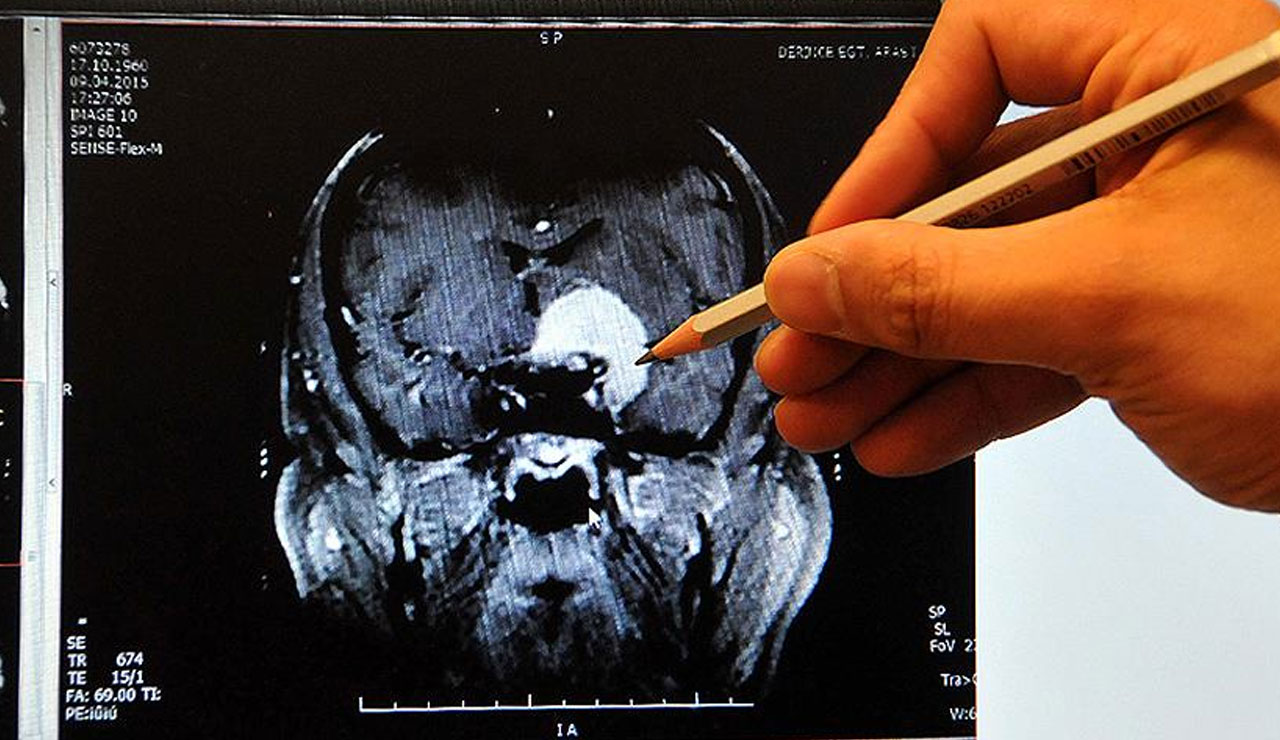

Prof. Dr. Küçükkaya, "Ağır Covid-19 hastalarında hem akciğer küçük damarlarında hem de kalp ve beyin damarlarında tromboz görülme sıklığı yüksektir. Bu durum bu hastalarda en önemli ölüm sebebidir" dedi.

Bütün ağır infeksiyonlar sırasında, mikroplar veya toksinlerin dokularda ve damarlarda hasara sebep olduğunu hatırlatan Prof. Dr. Küçükkaya, bağışıklık sistemi mikroplarla savaşırken açığa çıkan maddelerin pıhtılaşma sistemini uyardığını belirterek “Amaç mikropları pıhtı ağıyla çevirmek ve kana karışmalasına engel olmaktır. Ağır infeksiyonlarda bazen bu süreç kontrolden çıkabilir. İnfeksiyon alanında ve vücudun başka yerlerinde pıhtılar oluşabilir. Ağır Covid-19 hastalarında hem akciğer küçük damarlarında hem de kalp ve beyin damarlarında tromboz görülme sıklığı yüksektir. Bu durum bu hastalarda en önemli ölüm sebebidir. Obezite, diyabet, kalp hastalığı, kanser gibi zaten pıhtı riski yüksek hastalarda Covid-19 hastalığından ölümlerin fazla olmasının da en önemli nedeni budur” diye konuştu.